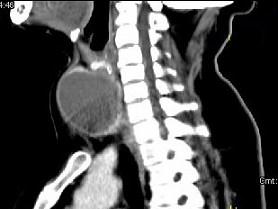

问题 女,56岁 ,发现颈部肿块一月余,CT如图所示,最可能诊断为 ( )

选项 A、甲状腺腺瘤 B、甲状腺脓肿 C、甲状腺乳头状癌 D、甲状腺原发淋巴瘤 E、甲状舌管囊肿

答案 A